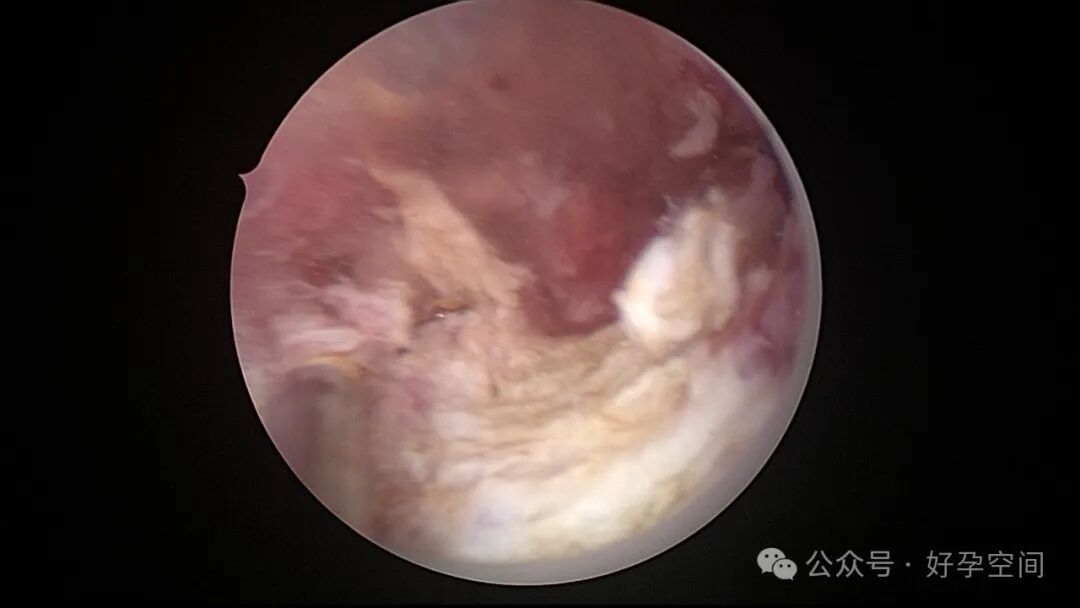

病例1:32岁,G8P3,剖宫产3次,本次停经50+天,计划外妊娠,宫腔镜辅助下清宫,见剖宫产瘢痕憩室,宫腔后壁2.5cm*2.0cm组织难以清除,宫腔镜电切送病检,病检结果为宫腔妊娠组织。

病例2:32岁,G3P1,剖宫产1次,本次停经60+天,稽留流产,宫腔镜辅助下清宫,宫腔广泛粘连,单极电针分粘。术后19天宫腔镜二探,宫腔后壁见1.0cm*1.0cm组织凸起,宫腔镜电切送病检,病检结果为宫腔增殖期样子宫内膜,另见血凝块及纤维素样坏死组织,浅肌层内可见少许滋养叶细胞(病理医生曾与临床医生沟通,病理图片跟超常胎盘部位反应很相似,但最后仅给出了以上病检诊断)。

病例3:26岁,孕产史不详,本次停经60+天,稽留流产,宫腔镜辅助下清宫,见剖宫产瘢痕憩室,左侧宫角2.0cm*1.5cm组织凸起,难以清除,宫腔镜电切送病检,病检结果为蜕膜组织及平滑肌组织。

病例4:34岁,G3P1,顺产1次,本次停经40+天,计划外妊娠,宫腔镜辅助下清宫,宫腔前壁2.cm*1.0cm组织难以清除,家属拒绝切除送病检,术后2周复查B超,宫腔查见1.1cm*1.0cm占位,无血流信号,门诊随访。